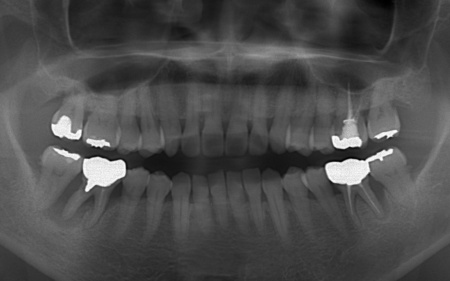

| カウンセリング | 拝見したところ、上下左右の奥歯計8本(第1大臼歯、第2大臼歯)に重度の歯周病が認められました。 歯周病は歯を支えている骨や歯ぐきに炎症が起こる病気です。進行すると歯がぐらついたり、噛む力が弱くなったりします。 さらに悪化すると歯を失う可能性が高くなるだけでなく、周囲の歯にも影響が広がることがあります。 特に下の奥歯2本(左右第1大臼歯)は歯を支えている骨が著しく減少して歯が大きく揺れており、治療して温存することは難しい状態でした。 また、左上の奥歯(第1大臼歯)は過去に詰め物で治療されていましたが、その下で虫歯が再発しています。 以上のことから、下左右の第1大臼歯は抜歯後に歯を補う治療、その他奥歯の治療、再発した虫歯の治療が必要と診断しました。 |

診断結果を踏まえ、まず下左右の第1大臼歯については抜歯したあとにインプラントで補う方法を提案しました。

さらに虫歯が再発していた左上奥歯については、虫歯をしっかりと取り除いたうえで被せ物による修復治療を提案しました。 それぞれのメリット・デメリットを丁寧に説明したところ、治療計画に同意いただきました。 まず、歯周基本治療から開始しました。 下左右の第1大臼歯を抜歯し、その部位にインプラントを埋め込む手術を行いました。同時に、インプラントの隣にある下の第2大臼歯に対して歯周組織再生療法を施しています。 また、左上の奥歯は虫歯を取り除いたあと、歯の形を整えて型取りを行い、最終的にジルコニアクラウンを装着しています。 段階的に治療を進め、すべての治療を終了しました。 |